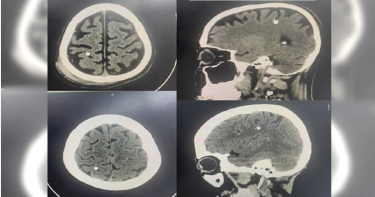

喝到腦萎縮!醫曬「酗酒者」掃描照揭恐怖後果:跌倒就可致命

喝酒可能誤事,酗酒更會讓大腦萎縮!國外有名醫師在社群曬出酗酒者與一般人的大腦掃描照對比圖,勸大家千萬不要酗酒,否則大腦不只萎縮、更容易發生腦損傷,還會引發造成嚴重後果的多種疾病。泰國神經外科醫生帕拉查(Pracha)在TikTok曬出一般車禍與酗酒車禍患者的腦部掃描照,指出該名54歲的長期酗酒男性,某天發生意外撞到頭被送院治療,但他的腦部比起53歲、遭遇類似車禍的未酗酒男傷患明顯不同。(圖/翻攝自TikTok)兩張掃描照一對比,可見酗酒者腦部的「黑色陰影」,也就是俗稱腦皺褶的腦迴變得光滑,整個大腦也出現萎縮、形狀改變,目視即可見酗酒者大腦比一般傷患大腦「離周圍的頭骨更遠」。帕拉查表示,長期酗酒不只會導致大腦萎縮,還更容易發生腦損傷,光是普通跌倒就可能發生腦出血,且酗酒也會導致糖尿病,以及血壓、血脂等慢性病指數更難控制,還增加腦性麻痺、殘疾與死亡風險。